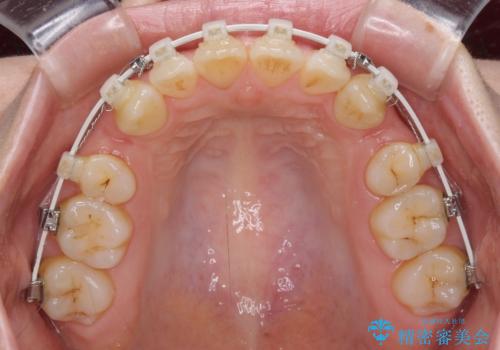

- 矯正装置

- 審美装置

- 1年9ヶ月

- 10-30回

- 上の前歯の飛び出した感じを改善したいとのことで来院された患者様です。

上顎左右第一小臼歯2本、下顎左右第二小臼歯2本を抜歯し、ワイヤー装置にて口元を引っ込めるよう矯正治療を行うこととしました。